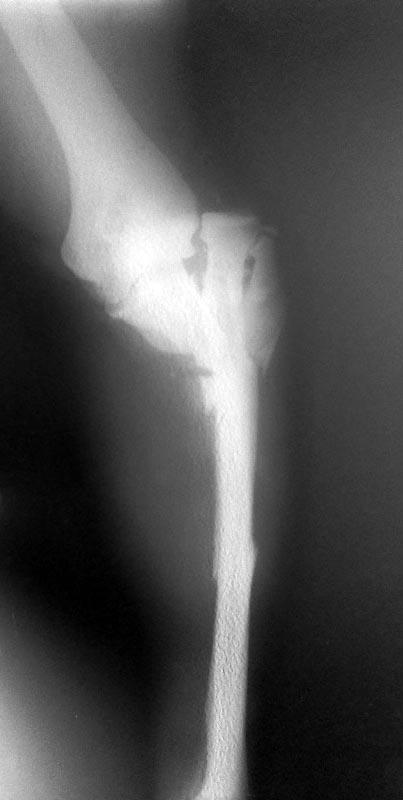

Здравствуйте, уважаемые коллеги. Пацент 36 лет, травма в ДТП открытые

переломы с обширными рваными ранами, которые удалось ушить и, возможно

заживут первично. При поступлении- ПХО ран, шов надколенника

полукисетами, вправление открытое луча, остеосинтез локтевой кости

спицами. Снимки прилагаются. Фото ран - тоже выложу. Прошу предложений о

тактике дальнейшего ведения. И хотел бы Ваше мнение о возможности

первично фиксации предплечья АВФ и в частности Илизаровским.